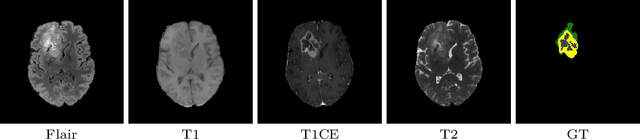

This paper proposes an adversarial learning based training approach for brain tumor segmentation task. In this concept, the 3D segmentation network learns from dual reciprocal adversarial learning approaches. To enhance the generalization across the segmentation predictions and to make the segmentation network robust, we adhere to the Virtual Adversarial Training approach by generating more adversarial examples via adding some noise on original patient data. By incorporating a critic that acts as a quantitative subjective referee, the segmentation network learns from the uncertainty information associated with segmentation results. We trained and evaluated network architecture on the RSNA-ASNR-MICCAI BraTS 2021 dataset. Our performance on the online validation dataset is as follows: Dice Similarity Score of 81.38%, 90.77% and 85.39%; Hausdorff Distance (95\%) of 21.83 mm, 5.37 mm, 8.56 mm for the enhancing tumor, whole tumor and tumor core, respectively. Similarly, our approach achieved a Dice Similarity Score of 84.55%, 90.46% and 85.30%, as well as Hausdorff Distance (95\%) of 13.48 mm, 6.32 mm and 16.98 mm on the final test dataset. Overall, our proposed approach yielded better performance in segmentation accuracy for each tumor sub-region. Our code implementation is publicly available at https://github.com/himashi92/vizviva_brats_2021